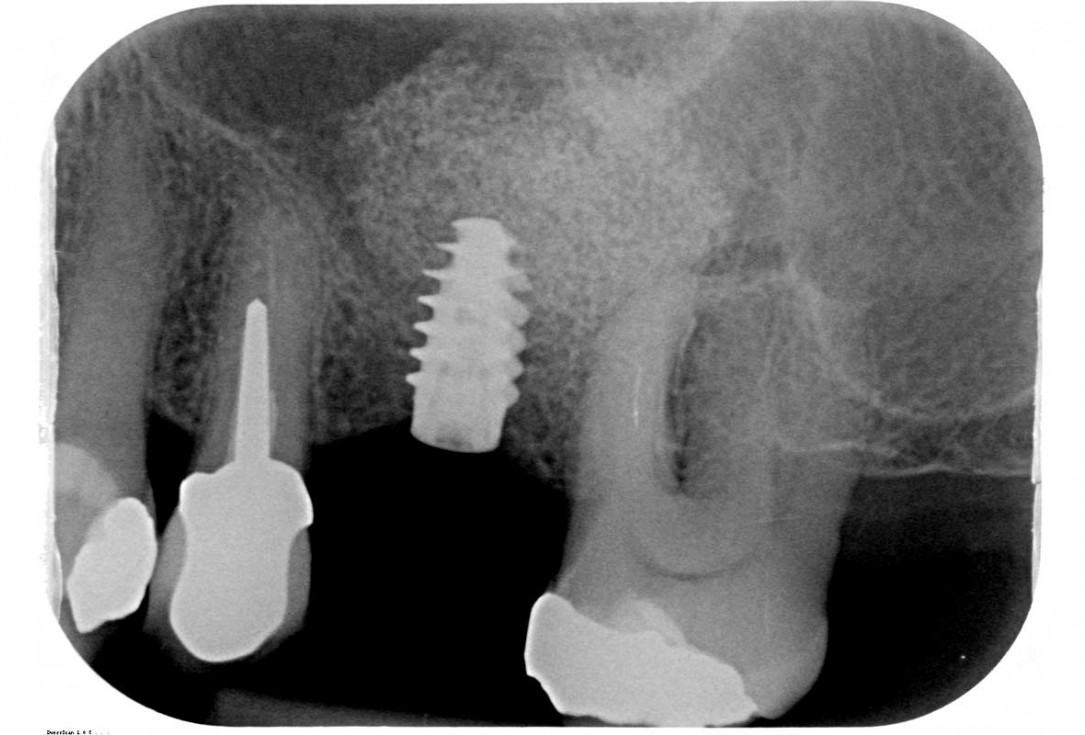

16/35 - X-ray after 5 monthsMaxillary sinus cyst removal using the Crocodile Technique and subsequent lateral sinus lift - Dres. C. Scognamiglio and A. Perucchi